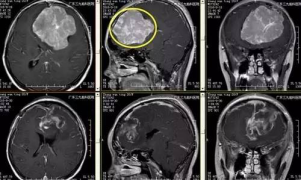

张女士,20岁,因间断头痛伴恶心、呕吐1年余,加重伴右侧肢体麻木1月,为求治疗,来我院就诊。入院后行头颅CT及MR示左侧额部大脑镰旁巨大脑膜瘤,大小约7.8×7.5×7cm,术前CTA提示肿瘤血管丰富,左侧大脑前动脉受挤压明显。由于瘤体太大,为保证患者的手术安全,经科室专家讨论研究决定,择期全麻下为患者行“左侧额部大脑镰旁巨大脑膜瘤切除术”,手术由张良主任主刀完成。经手术、术后康复理疗、物理治疗等系统的治疗后患者症状消失,康复出院。

↑手术前后对比